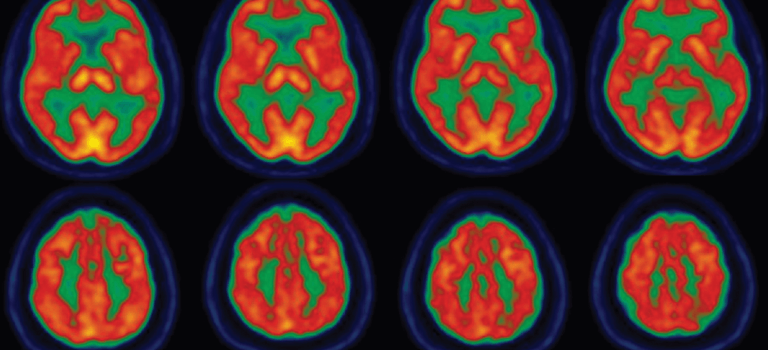

Jean-Philippe Langevin, MD, is a board-certified and fellowship-trained neurosurgeon specializing in the surgical treatment of movement disorders, epilepsy and psychiatric conditions.

He employs a variety of treatment modalities including deep brain stimulation (DBS), vagal nerve stimulation (VNS) and interstitial laser ablation. He is Director of the Restorative Neurosurgery and Deep Brain Stimulation Program at the Pacific Movement Disorders Center located at Providence Saint John’s Health Center and Providence Little Company of Mary Medical Center Torrance.

Dr. Langevin’s research interests include the application of neuromodulation to treat neuropsychiatric illnesses. He is the principal investigator of a trial evaluating non-invasive trigeminal nerve stimulation as a potential treatment modality for chronic post-concussive syndrome.

He is also the principal investigator for the clinical trial using DBS to treat post-traumatic stress disorder (PTSD) in combat veterans. This effort was recently reported in Popular Science. As part of this trial, Dr. Langevin performed the first ever surgery to address the symptoms of PTSD. He is also currently studying the potential application of DBS in substance use disorder.